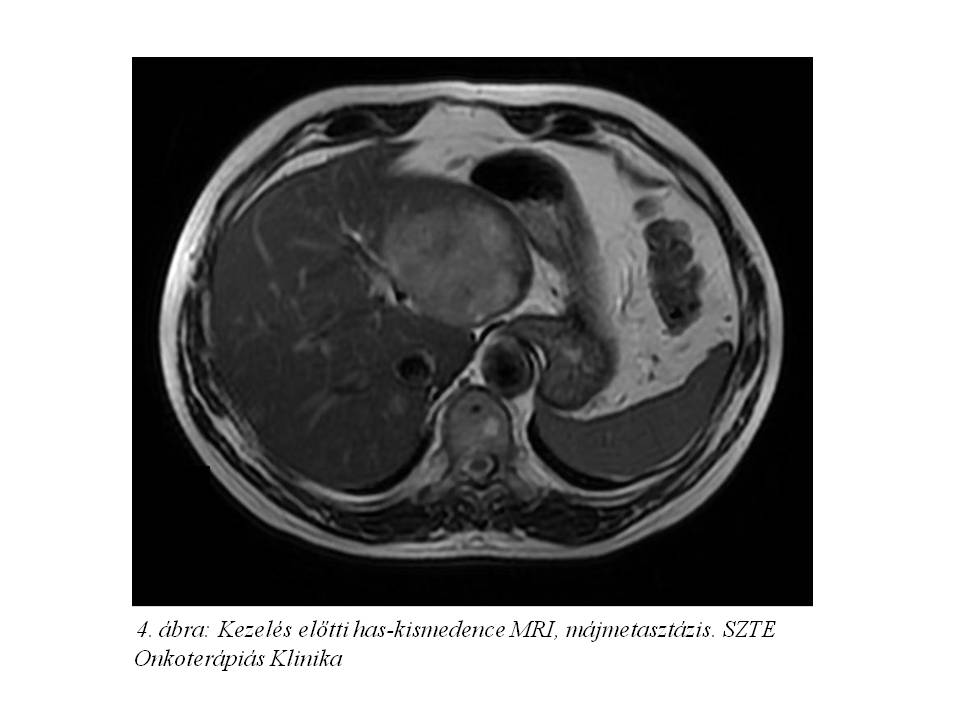

Tekintettel a diagnózis óta eltelt több hónapra re-staging hasi MR (4. ábra) és CT enteroklysis vizsgálat (5. ábra, 6. ábra, 7. ábra) történt. Az előbbi változatlan állapotot írt le, azonban az utóbbin a terminális ileum kezdeti szakaszán kb. 1,1x1,8x10 mm-es térszűkítő folyamat is ábrázolódott, mely megfelel a primer neuroendokrin tumornak.